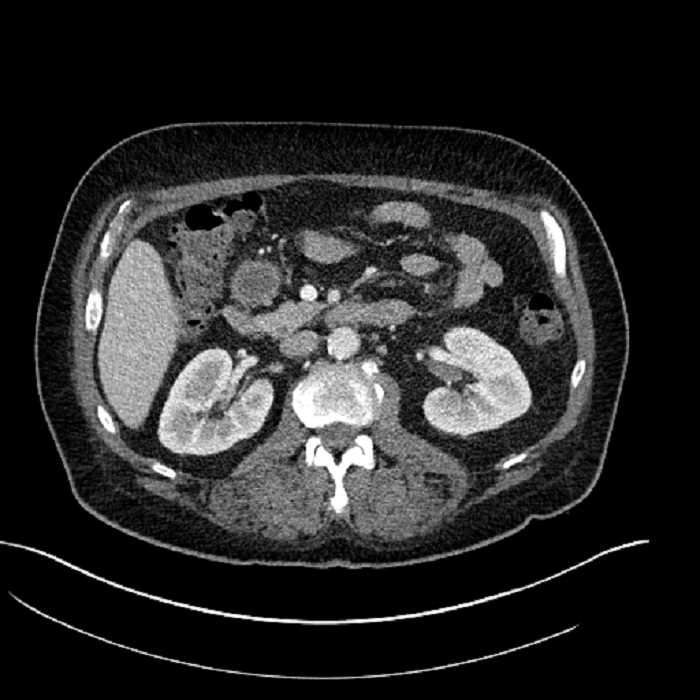

Age: 63

Sex: Male

Indication: Abdominal pain

• Large fluid density structure in hepatic segments 7 and 8 measuring 10 x 7 x 7 cm with internal septation and circumferential ill-defined low density compatible with edema

• Clearly marginated fluid density structure in segment 7 and several other scattered tiny hypodensities, which likely represent cysts

• Mild mural thickening of a segment of the sigmoid colon with adjacent fat stranding and a 1.5 cm fluid and gas collection along the tip of an inflamed diverticulum

• Loss of the normal fat plane between this collection and adjacent loops of small bowel, which demonstrate mural thickening

• Hepatic abscess

Acute sigmoid diverticulitis complicated by a small contained perforation and a large abscess in the right hepatic lobe. Additional small subcapsular abscesses along the anterior margin of the left hepatic lobe.

• The classic CT imaging appearance is a double target sign with internal low density surrounded by an internal enhancing rim (capsule) and a low density external rim (edema)

Hepatic abscess showing the double target sign with low density internally surrounded by a thin inner enhancing rim (red arrow) and ill-defined outer low density rim (yellow arrow). Blue arrow indicates an internal septation. Red arrows: additional smaller subcapsular abscesses. Red arrow: focal contained perforation associated with diverticulitis.